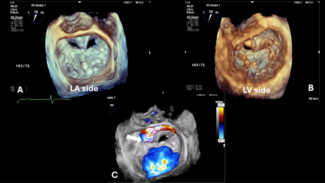

A 63-year-old man underwent mitral valve repair with a 28-mm Cosgrove-Edwards annuloplasty ring (Edwards Lifesciences) in 1999 due to severe primary mitral regurgitation. He did well until recently, when he was recurrently admitted with...